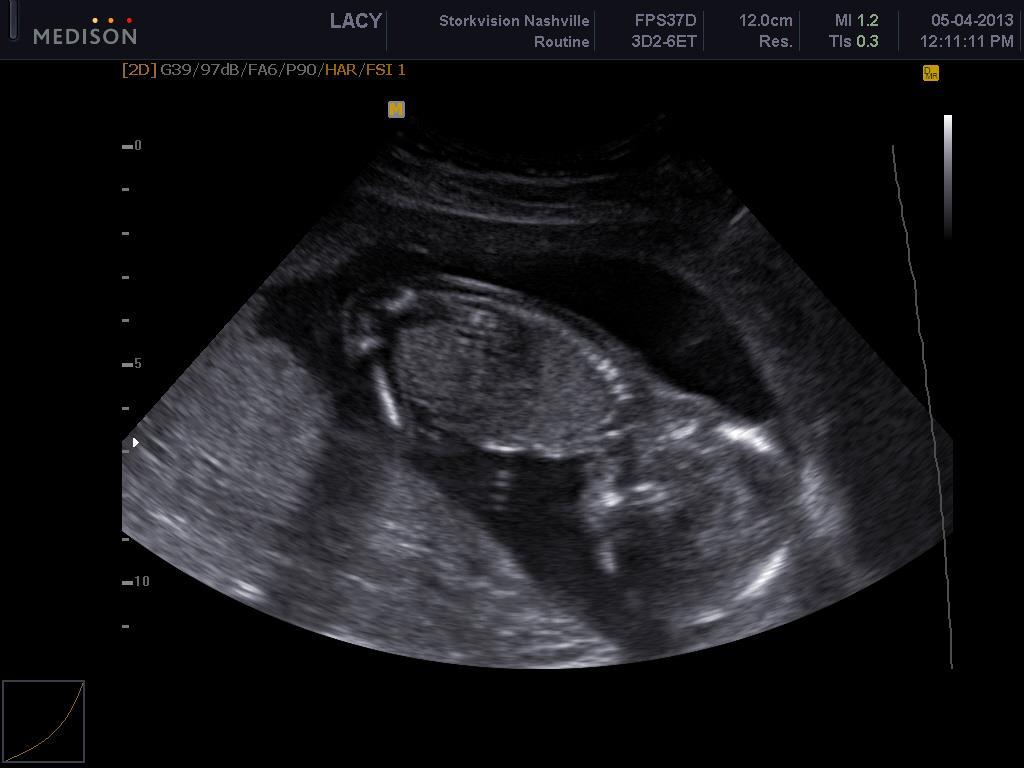

Photo May 7, 2013 at 2:25 PM Meet William Jonathan LaCour, due in October. Its a boy! Wheeeee! Jonathan LaCour